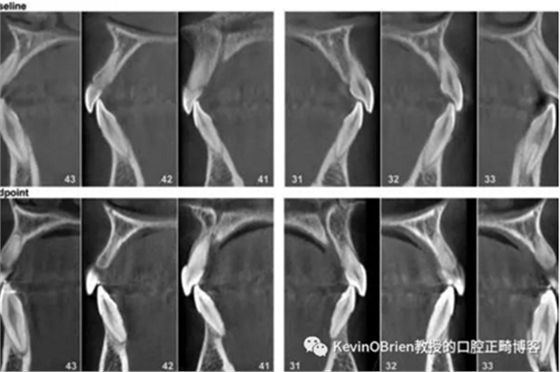

他們選定了30篇文章,其中6篇是RCT,6篇是前瞻性非隨機(jī)化研究,還有18篇是回顧性研究。這些文章包含了年齡從11.4歲到26.6歲的1219位患者。

他們覺得其中4項(xiàng)試驗(yàn)存在高偏倚風(fēng)險(xiǎn)。重要的是,所有的非隨機(jī)研究都有高偏倚風(fēng)險(xiǎn)。

他們在文章和詳細(xì)的表格中展示了大量數(shù)據(jù)。我將我認(rèn)為的主要發(fā)現(xiàn)濃縮在下面這個(gè)表里。

OIRR平均值及95%置信區(qū)間(mm)

固定矯治器0.8 (0.5-1.0)

上頜快速擴(kuò)弓0.4 (-1-0.7)

前牙0.9 (0.6-1.1)

后牙0.2 (-0.3-0.8)